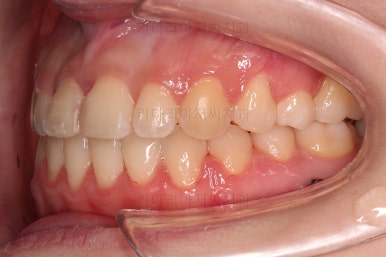

초진 시, 입안의 모습입니다.

아래 중앙선이 윗니의 정중선에 비해 우측으로 많이 쏠려있고요.

전반적으로 아래 치열이 우측으로 가 있어서 특히 송곳니 부분에서의 반대교합이 두드러졌어요.

(아래 송곳니가 위 송곳니보다 밖에 나와있는 상태)

폭이 맞아지고 치아 배열을 조금 시행하니 송곳니 부분에서의 반대교합이 금새 개선된 것을 알 수 있으실거에요.

가지런한 느낌, 교합, 중앙선, 반대교합 등 모든 면에서 개선이 되었고요.